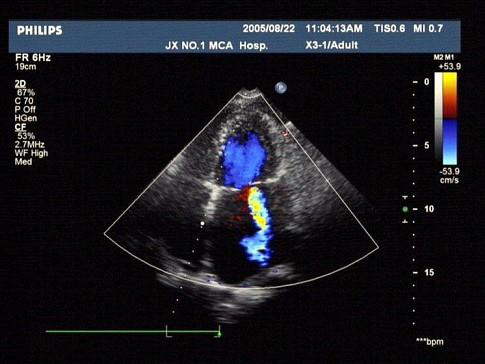

问题 如图,初步超声诊断为?(?)

选项 A.二尖瓣返流 B.三尖瓣返流 C.主动脉瓣返流 D.肺动脉瓣返流 E.以上均不是

答案 A